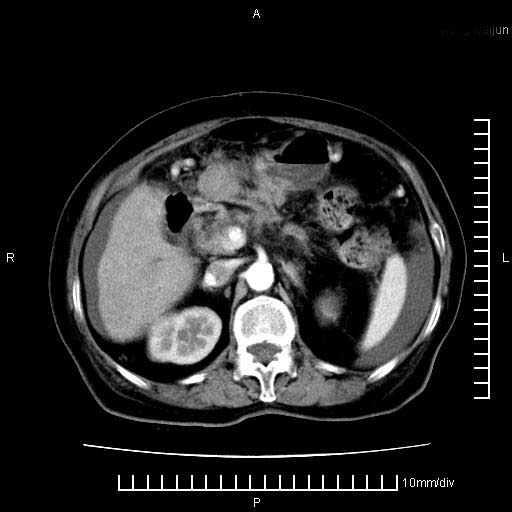

标题: CT28280:腹部增强:女性,80岁

上腹疼痛月余,外院核磁诊断胰腺癌。现临床示右下腹可明显触及包块,可片子上怎么没有看到?

1.胰腺颈体部癌。

2。腹腔积液。

3。右胸腔积液,伴右肺下叶部分萎陷。

4。右肾盂囊肿。

胰腺体部癌累及周围器官,腹膜、粘连

1。胰腺ca伴腹膜腔转移

2。肝左叶低密度灶,考虑转移可能

胰腺体部癌累及周围器官,腹膜、粘连,临床摸到的可能是粘的组织

胰腺结构模糊,胰尾部见囊性包块,周围脂肪密度增高,左肾前筋膜增厚,胸水、腹水。不符合胰腺ca伴腹膜腔转移。考虑胰腺炎伴假性囊肿形成、胸腹腔积液。

右肾盂囊肿。

1)考虑胰腺癌并胰腺假性囊肿形成。2)肝内低密度灶,不排除转移。3)右肾盂积水。4)腹水。5)右侧胸腔积液并右肺下叶部分膨胀不全。